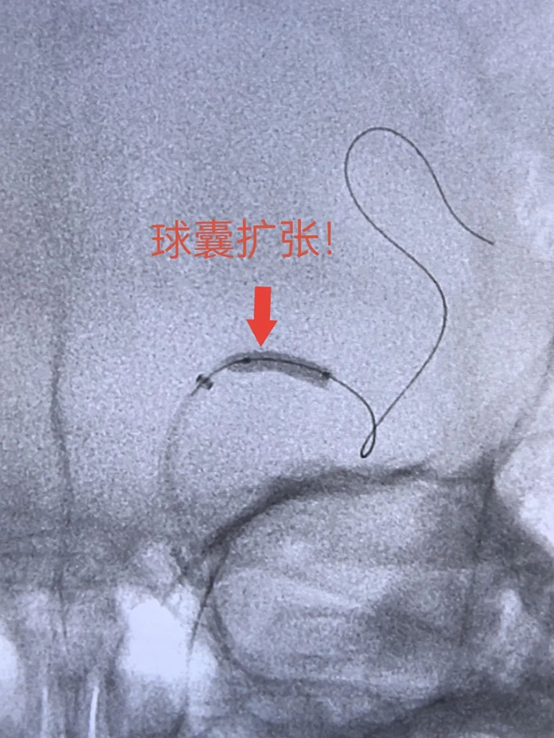

神经外科主任医师陈谦、主治医师张洪武采用“抽吸+球扩+抽吸”策略,凭借高超且精准的操作,手术开始后仅15分钟即实现血流恢复,患者术中右侧肢体明显恢复!继续观察15分钟,血流通畅良好,顺利结束手术。